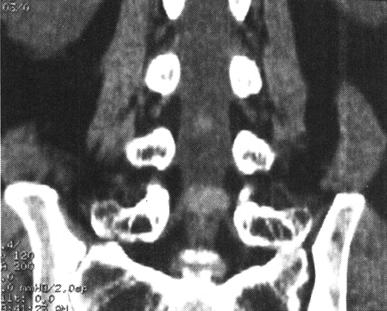

(四)CT脊髓造影或脊髓造影后CT

CT与MR出现以来,脊髓造影已不再常规使用。但在复杂的脊柱损伤CT扫描中,无法显示硬膜囊内结构,使用水溶性非离子型鞘内造影剂进行脊髓造影后CT扫描(CTM)扩展了CT在脊髓损伤中的应用(图7-11)。

图7-11 脊髓造影后多排螺旋CT扫描矢状面重建,可区分脊髓、神经根。蛛网膜下腔充满造影剂呈高密度,而脊髓、神经根呈中等密度

传统的脊柱造影需要病人配合医生转动体位来控制造影剂在椎管里的流动,而对脊髓损伤的病人,这可能是致命的危险,俯卧位似乎比侧卧位及仰卧位更易导致椎骨脱位。CrM对神经系统损伤病人的术前评估更有价值。当MR成像更普及时,脊髓X线摄影术和CTM的运用将逐步减少。

当脊髓、马尾神经被软组织压迫或怀疑硬脊膜撕裂时,CTM扫描就显得特别有用。一般来说,鞘内注射造影剂是通过C1~C2穿刺,以减少搬动病人所带来的潜在损伤。CTM的优点在于:①脊髓更好地显影;②提高软组织损伤压迫脊髓的诊断显示率,例如椎间盘突出或硬膜外血肿;③脊髓神经根的硬膜撕裂的诊断。CTM较之传统X线体层摄影、脊髓造影和CT平扫在脊椎骨折损伤的神经定位方面有较大的优越性。脊髓压迫可以在X线脊髓造影中显示,但在CTM中显示更清楚直观。在严重压迫的情况下,髓内创伤的诊断是非常困难的。硬膜外不同程度的压迫可导致脊髓不同程度的破裂。当造影剂充盈硬膜囊时,严重的脊髓损伤可出现脊髓缺损的征象。硬膜撕裂可导致造影剂外渗至硬膜外间隙。尽管撕裂的硬膜可自愈,但识别硬膜撕裂也是很重要的,因为撕裂可能导致多种后遗症,如脑膜炎、神经根内陷,脑脊膜突出或延迟神经损伤。CTM在全脊髓损伤病人诊断中的作用仍存在争议。